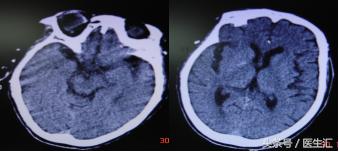

辅助检查:入院当日18:45头颅CT(见图7)

治疗经过:家属同意rtPA溶栓,19时开始rtPA50mg静脉注射2小时后意识转为嗜睡,右侧肢体肌力二级,NIHSS评分19分次日NIHSS评分6分7日NIHSS评分2分(见图8)

MRI示:左丘脑、左枕叶、小脑蚓部、桥脑急性脑梗塞(见图9)